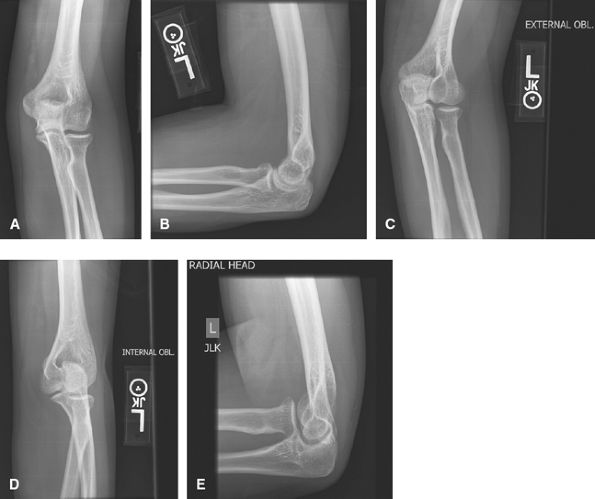

Trauma

Good to assess for otherwise occult radial head

fractures. Often AP, lateral, and radial head are enough for trauma. US

or MRI can assess for ligamentous or tendon injuries.

![]() |

Figure 10 (A) AP. (B) Lateral. (C) Lateral (external or radial) oblique. (D) Medial (internal or ulnar) oblique. (E) Radial head view.